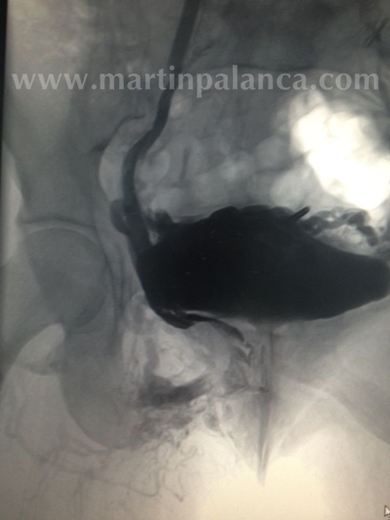

2ª)